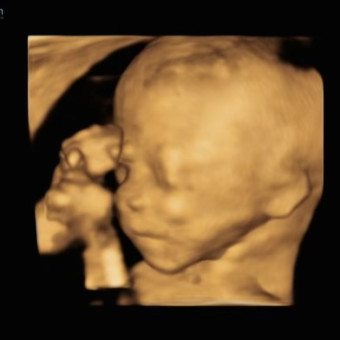

Erica & Tucker's Baby Registry

Erica & Tucker Sanders

September 22, 2023

Thank you for showering our baby girl with love!